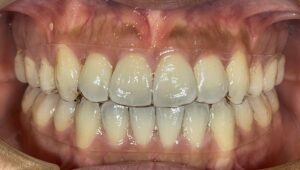

【再治療しないためには?】矯正治療で大切なポイントとは

矯正治療を受けたのに、数年後に歯並びが戻ってしまった…そんなご相談を受けることがあります。せっかく時間と費用をかけて治療したのに、再治療が必要になるのはできるだけ避けたいものですよね。

今回は「再治療を避けるために、最初の治療で大切なこと」「治療後に気をつけるべきこと」について、当院の視点からお話します。